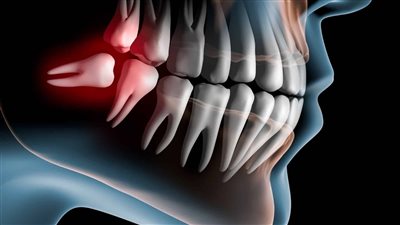

حالة من الرعب يدخل فيها الكثير عندما يكون أمام مرحلة الدخول في عملية خلع ضرس العقل.. بل يفضل الكثير تحمل الآلام على أن يخلع الضرس، وفي هذا التقرير سوف نعرض كم تستغرق عملية خلع ضرس العقل، فهو ينمو خلال الفترة العمرية من 17 سنة حتى 30 سنة، ويكون عبارة عن 4 ضروس في كل جهة اثنين، واحدة في الفك السلفي والآخر علوي.

- وكذلك مع حالات ضرس العقل المدفون.

وأضاف أخصائي غرس وتجميل الأسنان، أن عملية خلع ضرس العقل المدفون بنج كامل، وذلك لأن الطبيب يقوم بعمل ثقب في اللثة صغير، وبعد ذلك يزيل جزءا من العظم المحيط بضرس العقل، وذلك حتى يتمكن الطبيب من الوصول إلى الضرس.